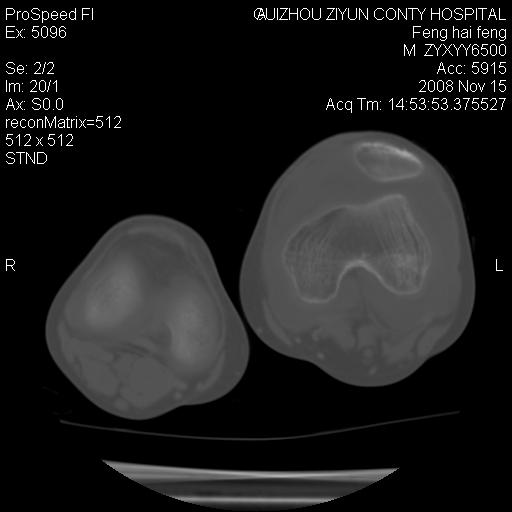

标题: CT16656:M 14Y 左膝关节肿胀一年余。其余病史不详。 [打印本页]

标题: CT16656:M 14Y 左膝关节肿胀一年余。其余病史不详。

考虑左侧髌骨结核;左膝关节滑膜肿胀、增厚,关节囊积液。

左膝滑膜型关节结核可能性大!支持!滑膜型关节结核主要ct表现:关节囊肿胀,积液,关节面见小破坏灶,并见点状死骨!

左膝滑膜型关节结核可能性大!支持!滑膜型关节结核主要ct表现:关节囊肿胀,积液,关节面见小破坏灶,并见点状死骨

好大的左腿!考虑左侧髌骨结核,左膝关节滑膜肿胀、增厚,关节囊积液。

左侧髌骨结核;左膝关节滑膜肿胀、增厚,关节囊积液